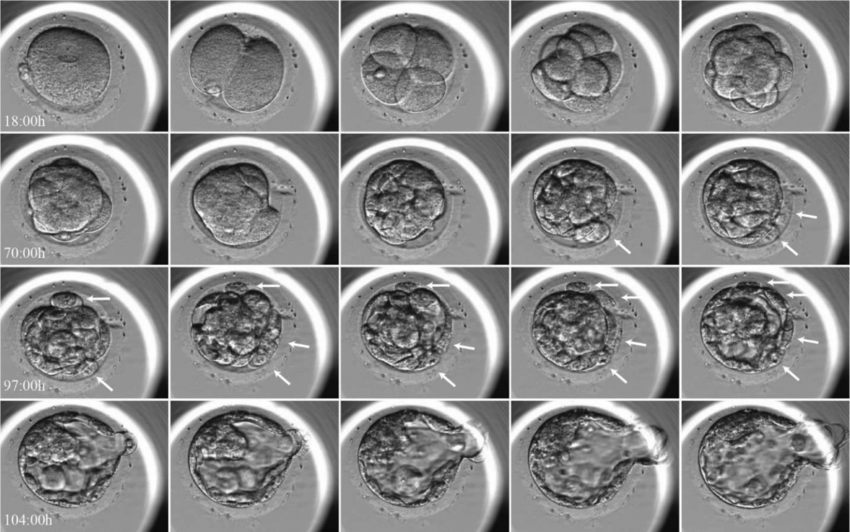

Klasik embriyo değerlendirmesinde embriyolar, belirli zaman aralıklarında mikroskop altında incelenir ve hücre sayısı, hücre yapısı ve simetrisi gibi morfolojik özelliklere göre derecelendirilir. Bu değerlendirme genellikle embriyo gelişiminin 3. gün ve 5. gün blastosist aşamasında yapılır.

Ancak bu yöntem, embriyonun yalnızca belirli anlarını gösterir; gelişim sürecinin tamamını yansıtmaz.

Time-Lapse Embriyo Takip Sistemleri (TLI), embriyoların inkübatör dışına çıkarılmadan, 24 saat boyunca kesintisiz olarak görüntülenmesini sağlar. Böylece embriyonun tüm gelişim süreci kayıt altına alınır.